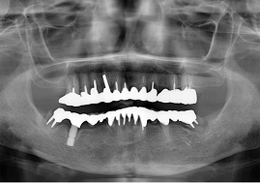

下顎のALL-ON-4①(下の歯のオールオンフォー)

-

- 主訴

- もともと入っているインプラントの周りが腫れ、残りの歯も動いているので力が入らない

- 治療内容

- 下顎右側に以前埋入したインプラントの撤去を行い、歯周病の進行が著しかった残存歯の抜歯を行うと同時にインプラントの埋入を行い、当日仮歯を装着した

- 治療費用

- 下顎ALL-ON-4:4,000,000円(税別)

- 治療期間

- 6ヶ月